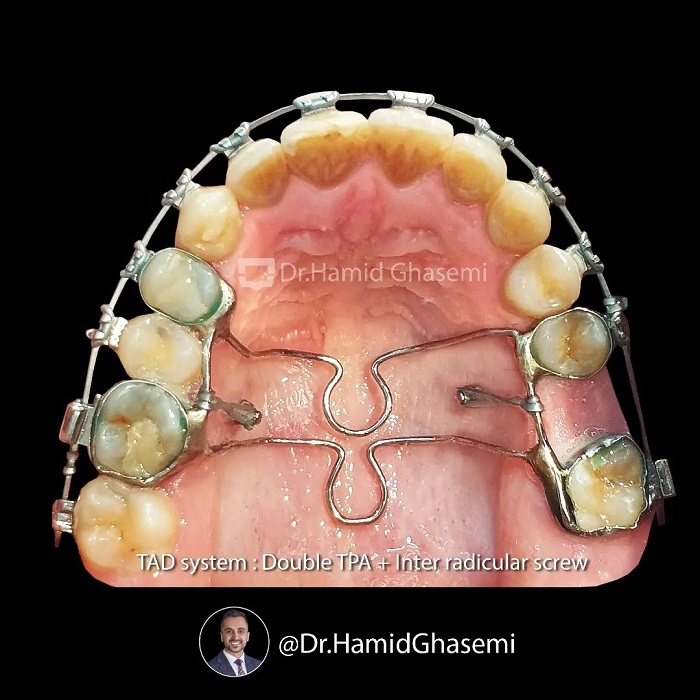

توتال ایمپکشن و توتال دیستالیزیشن بدون جراحی فک در فک بالا و به دنبال آن auto rotation(چرخش فک پایین به دنبال جابجایی فک بالا) مندیبل با استفاده از Tad system (ساخته شده از Double TPA اختصاصی متصل و مينی اسکرو). بیمار با سابقه انجام ارتودنسی ناموفق همراه با کشیدن دندان قدامی در فک پایین و ارجاع بیمار به جراح جهت انجام جراحی ۲ فک بعد از ۲ سال درمان ارتودنسی به امید انجام درمان مجدد بدون جراحی فک به کلینیک بنده مراجعه کردند و خیلی خوشحالم که در انتها به نتیجه دلخواه رسیدند. به تغییرات ایجاد شده در صورت (۱/۳ تحتانی ) و فکین بعد از درمان توجه کنید. ورق بزنید و نظر خودتون رو برامون کامنت کنید. 💪💪💪

🔺️Non surgical orthodontic total impaction and total distalization of maxillary arch followed by auto rotation of lower jaw using Tads system which customized by connected double TPA and mini intra radicular screws. This patient had history of unsuccessful orthodontic treatment with extraction of lower front tooth and both jaw surgery was offered to her by her former orthodontist after almost 2 years orthodontic treatment and she came all the way to our office to plan for non surgical orthodontic re-treatment and im glad that she is happy with result. Take note on significant changes done on overall facial(lower 3rd) and dentition. Slide and comment your opinion… 💪💪💪